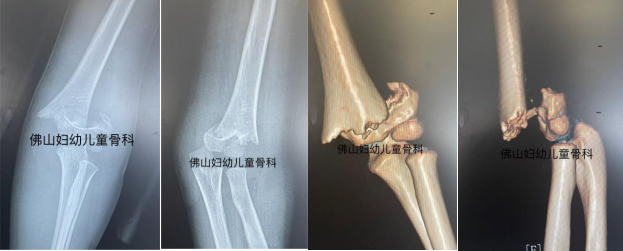

受伤X线片及CT图片:可见骨折粉碎并严重错位↓